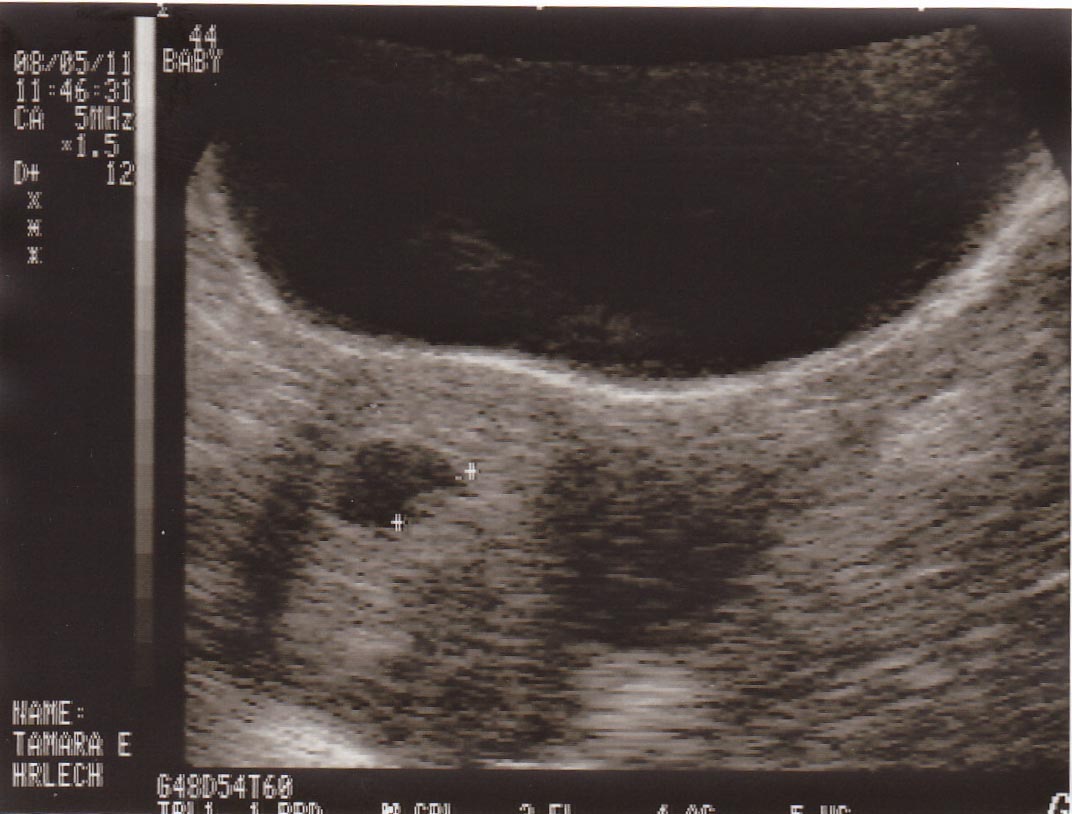

I have already gone and done all of my blood work and have an ultrasound scheduled for tomorrow afternoon, Aug 5...Chase's birthday. It would make such a special present if Chase could go but he wont be home in time from working in Blythe. He'll get the pictures when he gets home though.

The due date is March 23 2012, which makes me 7 weeks tomorrow. We wont know the sex until October, but we're already dying to know if its the daughter we've been dreaming of or a baby brother for Hunter. We are so thankful for this new blessing and pray for a healthy and happy pregnancy and baby.